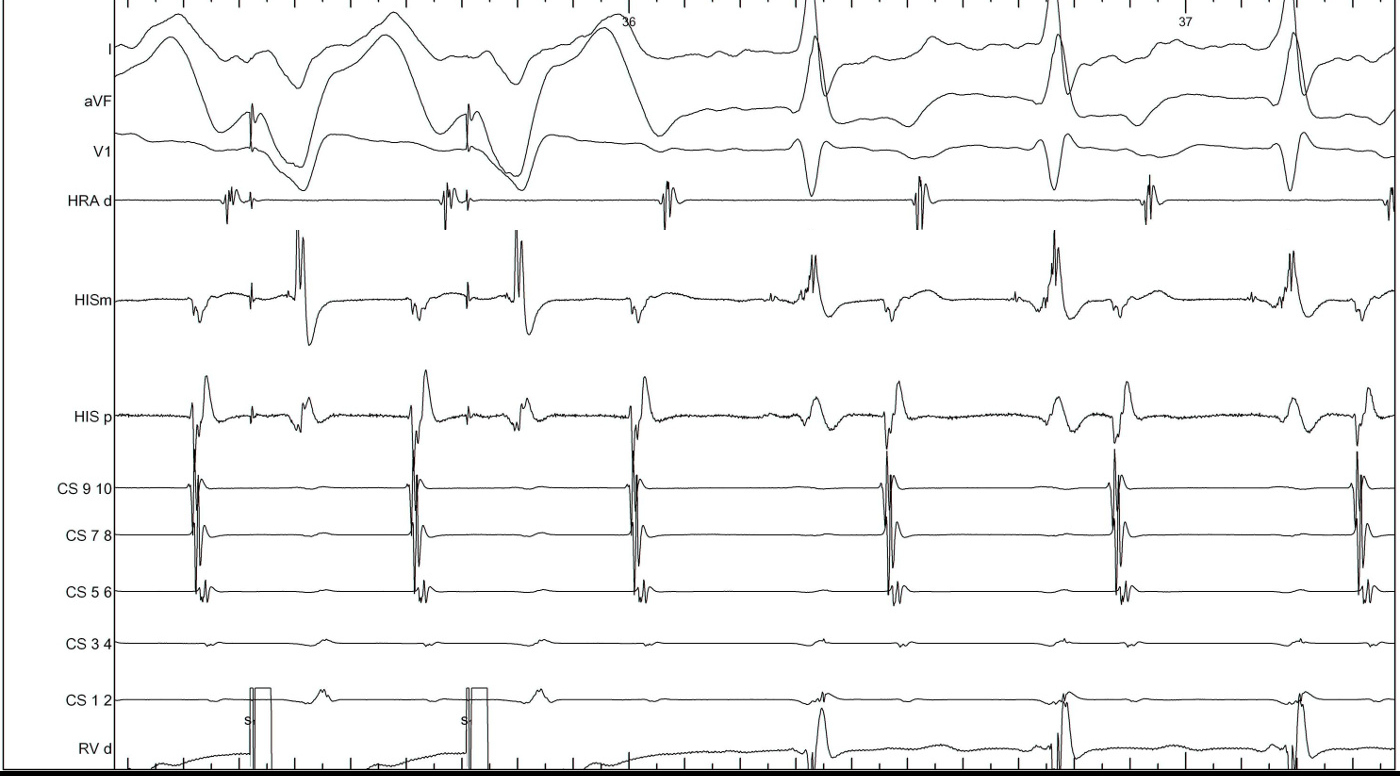

Narrow QRS tachycardia, central atrial activation, very short VA

typical_avnrt.jpg

Commonest Setting

• Regular narrow QRS tachycardia

• 1:1 VA

• Atrial activation central

• VA > 70 ms

SVT

svt.jpg